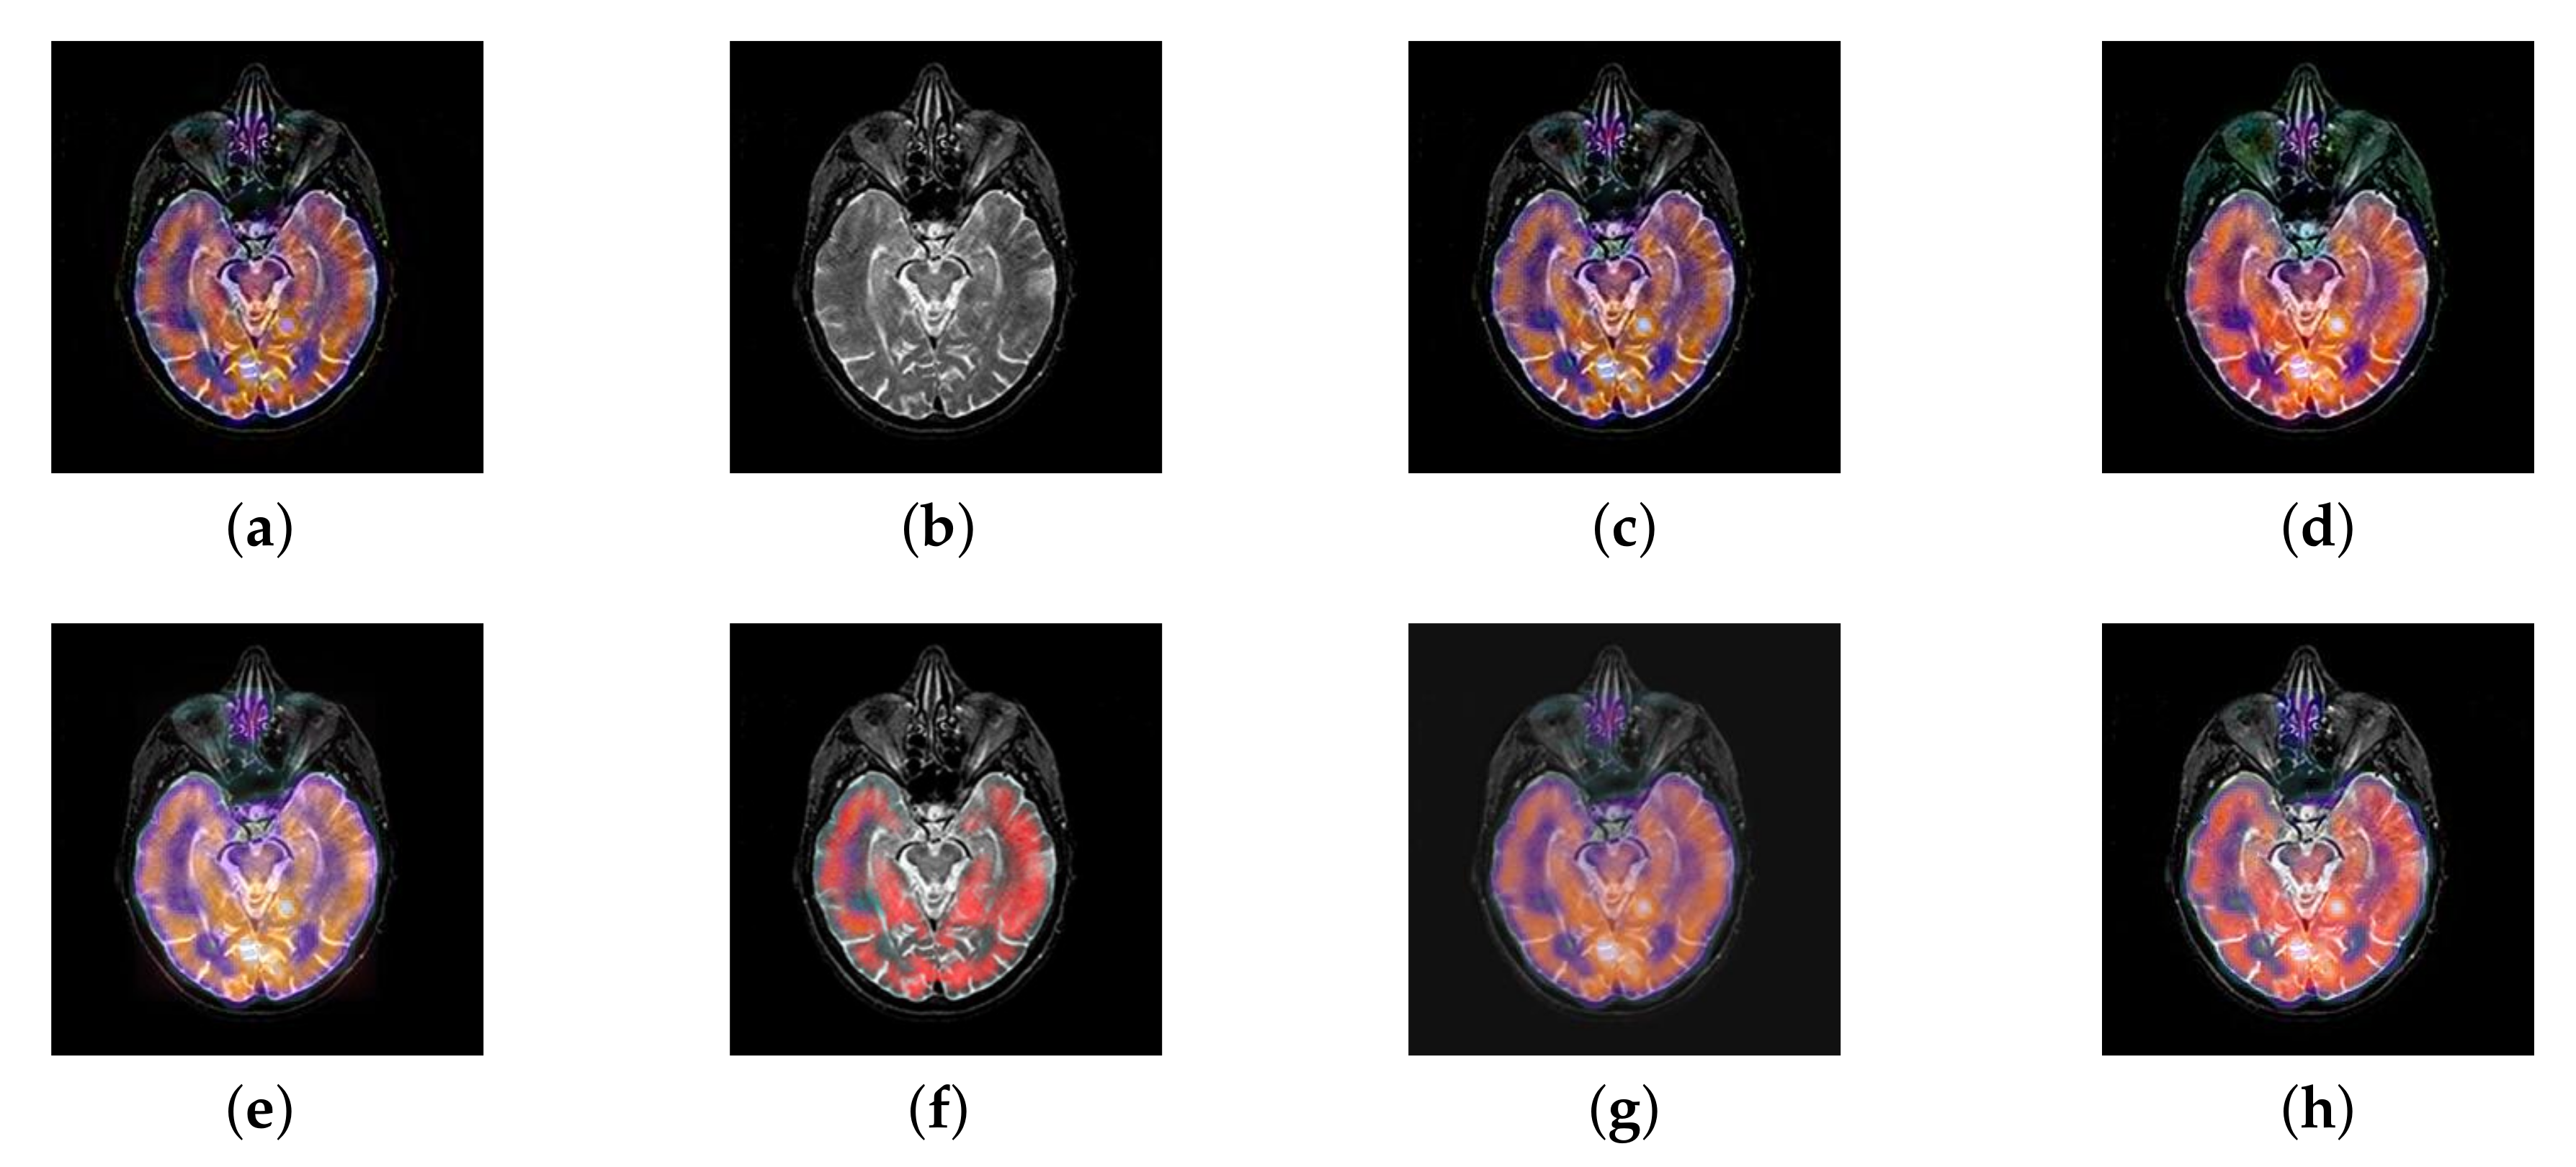

In this section, there are four image sets to fuse, each containing a MRI image and its corresponding CBF image in Figure 41. In Figure 42, Figure 43, Figure 44 and Figure 45, it can be seen that the structural information of fusion images obtained by our algorithm is complete. The color is not distorted, and the spectral features are natural. The fusion image based on DTCWT and NSCT algorithm have high color fidelity but less structural information. Other algorithms, such as IGM, LPSR, and FusionCNN, only focus on the structural information of the MRI image and ignore the color information of the fused image. Although the image structure information obtained by DDcGAN fusion algorithm is relatively complete, the edge of color information is not clear, which has a great influence on image contrast.

Figure 42.

Fused medical images obtained by different algorithms (Figure 41a,b): (a) DTCWT, (b) GFF, (c) NSCT, (d) LPSR, (e) IGM, (f) FusionCNN, (g) DDcGAN, and (h) FusionNet.

Figure 43.

Fused medical images obtained by different algorithms (Figure 41c,d): (a) DTCWT, (b) GFF, (c) NSCT, (d) LPSR, (e) IGM, (f) FusionCNN, (g) DDcGAN, and (h) FusionNet.

Figure 44.

Fused medical images obtained by different algorithms (Figure 41e,f): (a) DTCWT, (b) GFF, (c) NSCT, (d) LPSR, (e) IGM, (f) FusionCNN, (g) DDcGAN, and (h) FusionNet.

Figure 45.

Fused medical images obtained by different algorithms (Figure 41g,h): (a) DTCWT, (b) GFF, (c) NSCT, (d) LPSR, (e) IGM, (f) FusionCNN, (g) DDcGAN, and (h) FusionNet.